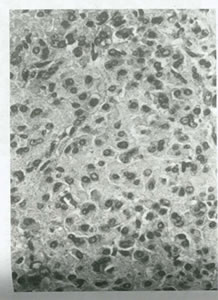

نماي ظاهري تومور سلول سرتولي- ليديگ بسيار متغير است. به طور كلي قطر متوسطي حدود 12-15 سانتي متر دارد وسطح برش داده شده معمولاً طلايي يا زرد است و ممكن است كيستيك باشد (شكل 43). در تومورهايي كه تمايز ضعيف دارند خونريزي و نكروز به طور شايع ديده مي شود در معاينه ميكروسكوپي، تومور از مخلوطي از سلول هاي استروماي گنادي نامتمايز سرتولي و ليديگ تشكيل شده كه ممكن است اجزاء هترولوگ داشته باشند يا نداشته باشند كه درجات و نسبت تمايز آنها متفاوت است. در ضايعاتي كه به خوبي تمايز يافته اند،سلول هاي سرتولي تشکيل توبول مي دهند و سلول هاي ليديگ در استروماي بينابيني ديده مي شوند (شكل 44). سلول هاي سرتولي از لحاظ سيتولوژي حاوي اشكال ميتوتيك نادري هستند. سلول هاي ليديگ ممكن است حاوي پيگمان هاي ليپوكروم فراوان يا كريستالوئيدهاي Reinke باشند. تومورهاي حد واسط و كم تمايز يافته با اجزاي نابالغ تر سرتولي و ليديگ همراه هستند.

- شکل 48:کارسينوم لوله فالوپ .کارسينوم سروز لوله فالوپ ظاهر ميکروسکوپي مشابه کارسينوم اوليه تخمدان دارد.در اين مثال سلول ها به صورت پا پي هاي ظريف و آشيانه هاي مجزا طبقه بندي شده اند.

شده است. در حالي كه نوع كم تمايز آن حاوي صفحات توپر سلولي با نواحي نكرز است(شكل 48).